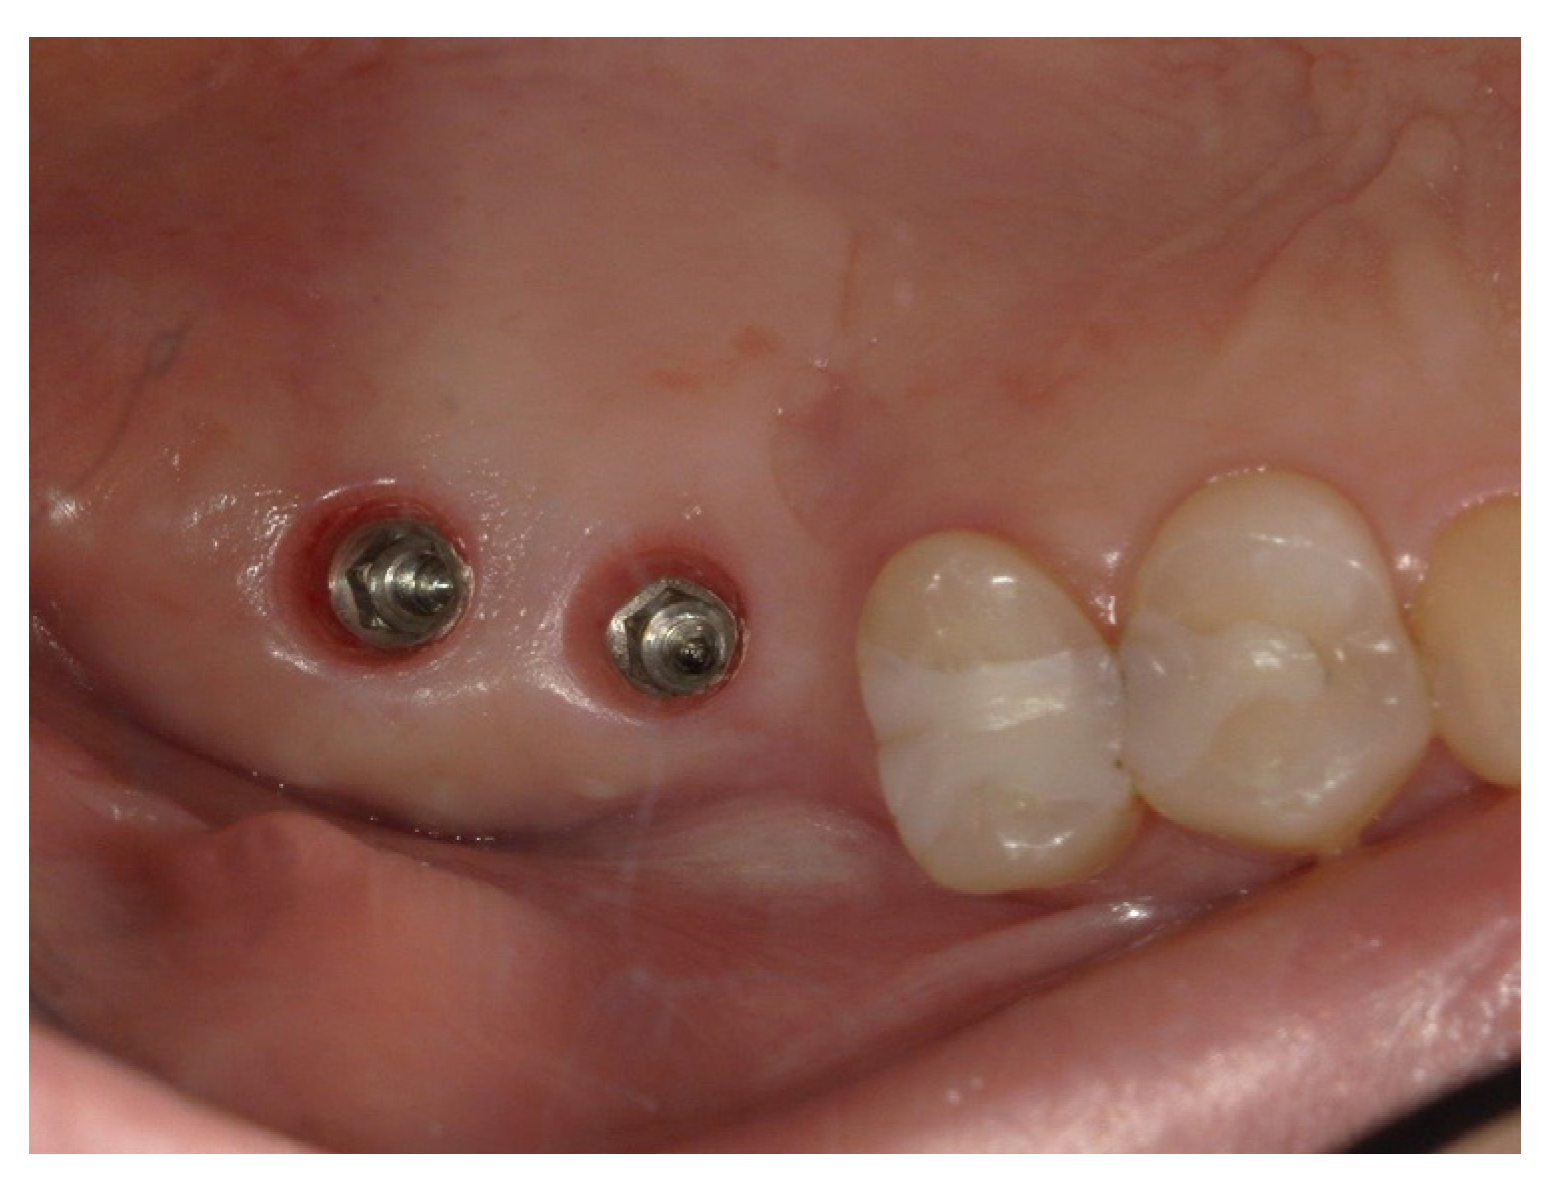

The final diagnosis of idiopathic osteosclerosis was confirmed. A six-month follow-up showed good healing, and prosthesis on dental implants was performed (Figure 8, Figure 9 and Figure 10).

Figure 8.

Good healing of soft tissues.